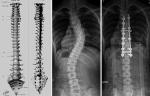

허리 디스크 등 검사서 휘게 보여 정확한 진단 결과 봐야성장기 학생 지속적인 관찰 및 치료 등 전문의 도움 필요 척추측만증이란 척추측만증은 일반적으로 등 또는 허리가 옆으로 휘는 병이라고 할 수 있다. 척추측만증이 있는 사람을 정면에서 보면 척추가 옆으로 휘어 보인다. 또 옆에서 보면 가슴과 등 사이 거리가 좁다. 정상인보다 등은 약간 굽어있고, 허리는 앞